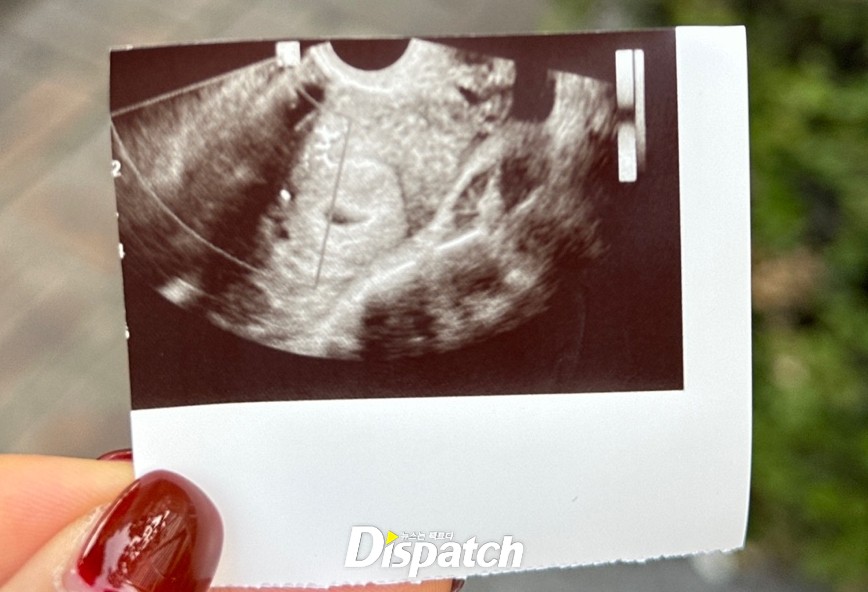

A씨는 6월 22일, 임신 테스트를 시도했다. 손흥민에게 2줄임을 알렸다. 그리고 이틀 뒤, 산부인과를 찾았다. hCG 결과는 5000mIU/mL. 임신 5~6주에 해당하는 수치였다.

손흥민 측도 A씨의 주장을 의심했다. 그도 그럴 게, 초음파 사진은 잘려 있었다. 이름 등의 정보가 나와 있지 않았다. 관계 시점과 임신 주수도 맞지 않는다고 생각했다.